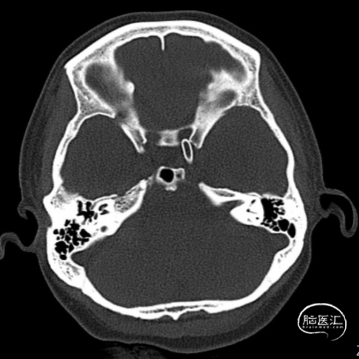

(A)

(B)

(C)

(D)

(E)

(F)

A:准备定位后打开Surpass Streamline头端于Catalyst 5。

B:缓慢回撤Catalyst 5,逐渐释放Surpass Streamline。

C:支架收尾。

D:Catalyst 5中间导管进行支架内按摩。

E:动脉瘤腔内可见造影剂滞留。

F:动脉瘤腔内可见造影剂滞留(另一角度)。

术后复查头部CT可见Surpass Streamline FD全程无狭窄,贴壁满意。患者无神经功能缺损表现,医嘱离院。